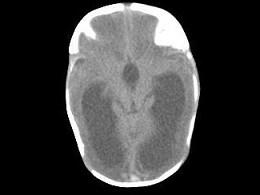

问题 1岁,女,头颅呈球状,颅骨透光试验阳性,请结合CT图像选择最可能诊断 ( )

选项 A、先天性脑积水 B、外部性脑积水 C、慢性双侧性巨大硬膜下血肿 D、水瘤 E、脑严重缺血

答案 A